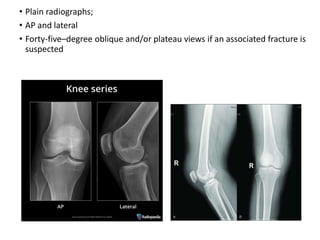

• Plain radiographs;

• AP and lateral

• Forty-five–degree oblique and/or plateau views if an associated fracture is

suspected